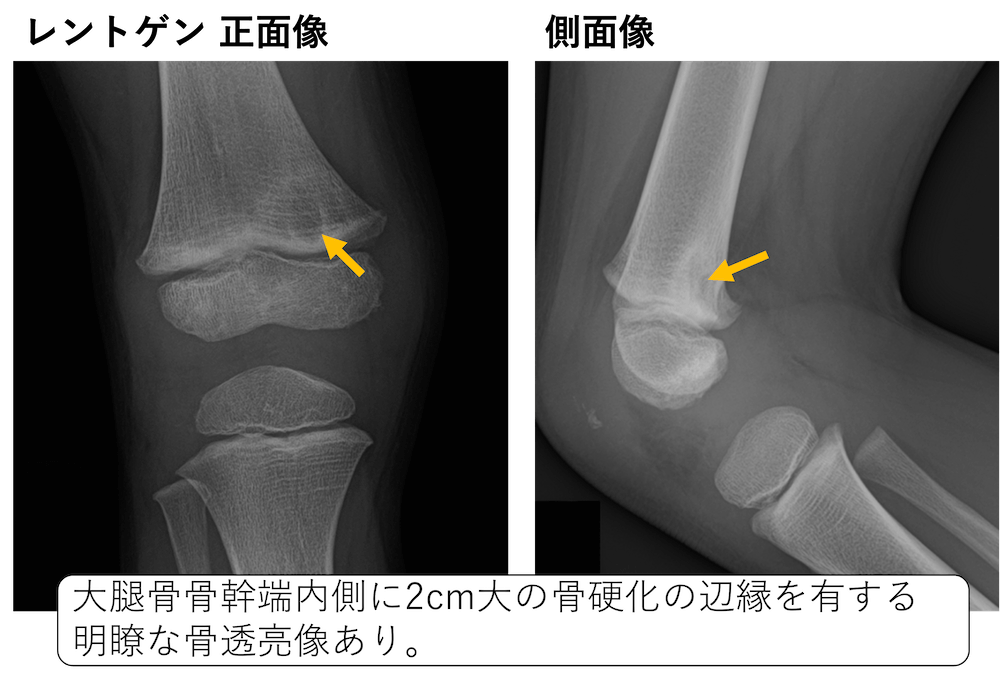

裁断済】マイヤース腹部放射線診断学 発生学的・解剖学的アプローチ。マイヤース腹部放射線診断学: 発生学的・解剖学的アプローチ。マイヤース腹部放射線診断学 発生学的・解剖学的アプローチ。mochi*°様✳︎ 小さなスコーンとポルポロン * スコーン 2月*。「マイヤース腹部放射線診断学 発生学的・解剖学的アプローチ」太田 光泰定価: ¥ 15400円+税即購入OKです(^^)・裁断済みです。書き込みはなく綺麗な状態です。裁断してある中古品であること、素人による裁断であることをご理解のうえ、ご購入下さい。神経質な方は購入をお控えください。・1-2日で発送致しますが、週末や連休中は発送が休み明けになることがあるかも知れません。。徹底的解剖学 | 黒澤一弘(かずひろ先生)による解剖生理学講座。綴じ口より裁断されておりバラバラの状態です。vol2 岩越真一先生(放射線医学 助教) | 奈良県立医科大学。グレイ解剖学 原著第5版 / Anatomy 今日も明日も/グレイ解剖学。裁断しているため、「傷や汚れあり」 にました。福井大学における革新的な画像医学教育への挑戦─ITとAiをベース。ポータブル電磁超音波探傷器 VOLTA2 (Innerspec Technologies。・ほとんど使用しておりませんが、多少のキズや小さな角折れ等あるかもしれません。黒澤一弘(かずひろ)解剖学IT教育・指圧師・ラダック on X。JRC2012 ziosoft/AMIN Seminar Report 超四次元画像。・梱包は丁寧に行うようにしておりますが、配送中の破損は保証できませんので、ご了承下さい。徹底的解剖学 | 黒澤一弘(かずひろ先生)による解剖生理学講座。画像診断を学ぼう 単純X線からCT・MRI・超音波まで 第2版。その際はご容赦下さい。【裁断済】小児・成育循環器学 改訂第2版